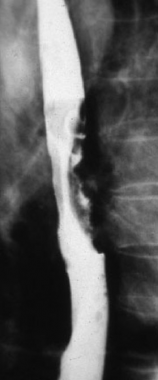

Barrium swallow

See narrowing of the oesphagus from tumour

Also take biopsy